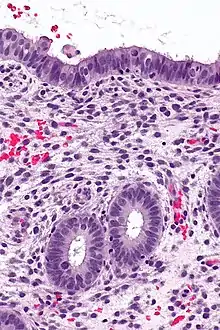

![]() | Lepromatous leprosy | Skin biopsy showing epidermal atrophy and multiple dermal infiltrates. | Category: Histopathology of leprosy | Leprosy |

![]() | Tuberculoid leprosy | Skin biopsy showing multiple peri-appendageal granulomas. | Category: Histopathology of leprosy | Leprosy |